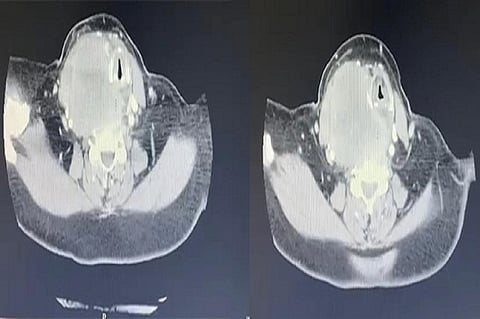

وقال د.طلال الجهني استشاري جراحة الأنف والأذن والحنجرة وأورام الرأس والرقبة: إن المريضة وهي في العقد السادس من العمر راجعت العيادة، وهي تعاني من أعراض حادة، تتمثل في صعوبة بالغة في التنفس والبلع والكلام، وأخضعت على الفور لفحوصات طبية دقيقة؛ أبرزها الأشعة المقطعية، كشفت النتائج وجود الورم الذي كان ضاغطًا بشدة على الأوردة والشرايين الرئيسية في الرقبة والحنجرة والقصبة الهوائية والمريء؛ مما سبّب تلك الأعراض الحادة.

وأضاف د.الجهني أن الفريق الطبي قام بتحويل الحالة إلى العمليات مباشرة، وفي أول خطوة تمت معالجة ضيق المجرى التنفسي بوضع أنبوب داخل القصبة الهوائية بواسطة المنظار؛ لتأمين الأكسجين وحماية المجاري التنفسية للمريض، ومن ثم قام فريق جراحة أورام الرأس والرقبة بالمستشفى بإجراء جراحة دقيقة تم فيها إزالة الورم بالكامل، مع المحافظة على الأوردة والشرايين الملتصقة به، وقد تكللت العملية التي استمرت زهاء الساعتين -ولله الحمد- بالنجاح، وتم تحويل المريضة إلى جناح التنويم، وتحسنت حالتها الصحية باضطراد مع العناية الطبية الحثيثة التي حظيت بها إلى أن غادرت المستشفى بعد يومين وهي بحالة جيدة؛ حيث تخلصت من الأعراض التي قادتها إلى المستشفى.

ووصف د.الجهني، العملية بأنها كانت معقدة ودقيقة بالنظر إلى ضخامة حجم الورم وتمدده إلى مواضع ذات حساسية عالية؛ إذ إنه كان ضاغطًا على الأوردة والشرايين الرئيسية للرقبة، واستئصال الورم دون إلحاق الضرر بهذه الأوردة والشرايين يحتاج إلى فريق طبي متمرس ومتميز، وإلى مراكز ومستشفيات متخصصة، وتحظى بالأجهزة والتقنيات الحديثة التي تعين العنصر البشري في إجراء مثل هذه العمليات.